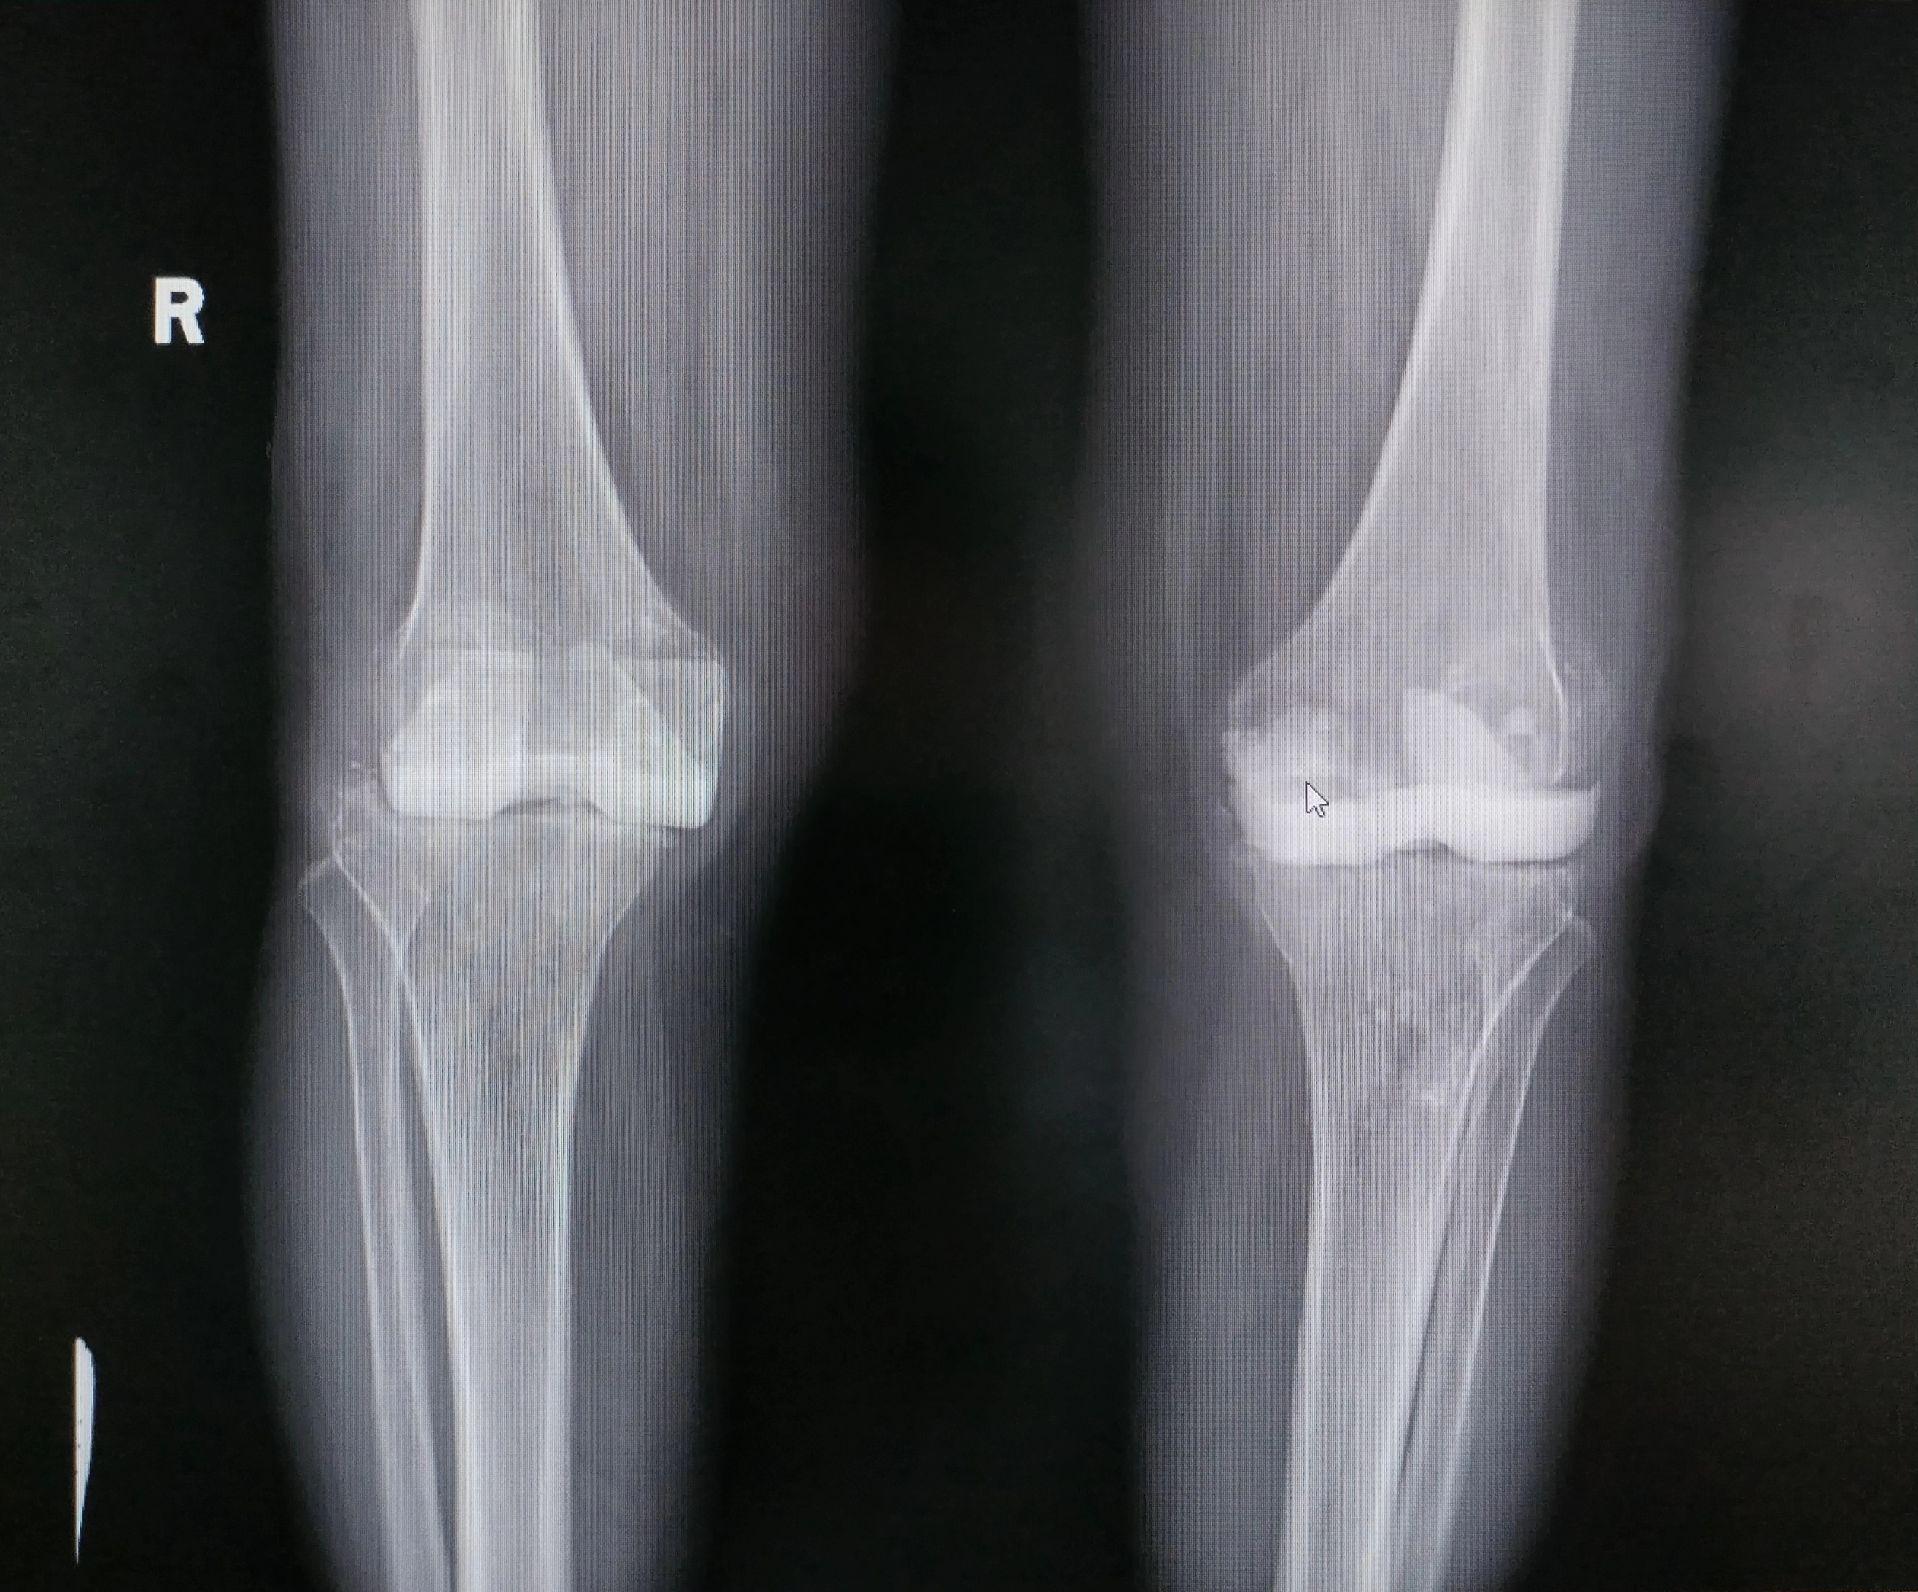

膝关节翻修术。双膝关节置换术后布氏杆菌感染(外院),清创旷置后二期翻修,重新走出自信的步伐。膝关节翻修

膝关节翻修术。双膝关节置换术后布氏杆菌感染(外院),清创旷置后二期翻修,重新走出自信的步伐。